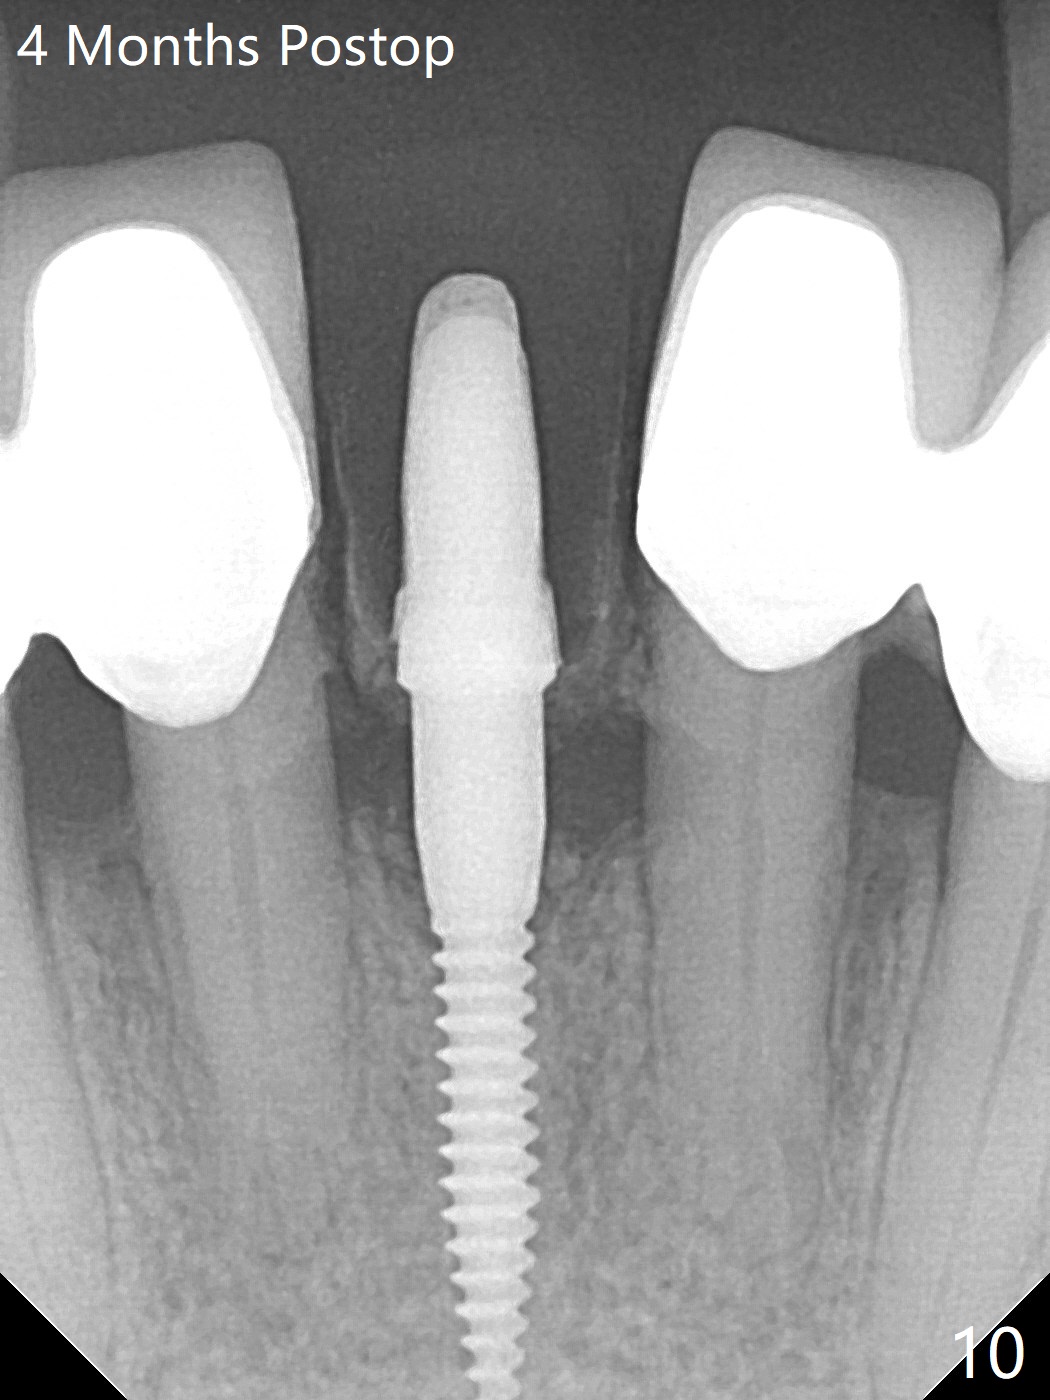

种植前与66岁女病人再次讨论下前牙正中种植可能产生不对称问题,她好像不在乎。术前检查显示下前牙正中间隙偏左(图一),处理似乎容易,但是牙槽嵴相当狭窄(图一 *,二 箭头)。牙槽嵴切除后(大约3 毫米宽(颊舌侧)),初期钻洞似乎偏移右边(图三),矫正后(图四),植入2乘10(4)毫米连体植体(图五,比预计小,因为骨质薄),放置骨粉(图五,六 *)和膜,缝合,制作即刻修复物(图七 T),病人满意,牙槽骨饱满了。术后一个多月临时牙冠取出修正,伤口愈合,由于植骨颊侧没有凹陷(图八),而舌侧隆起(图九:*,与图二术前对比)。其实病人不小心吃牛肉时损伤植体,疼痛几天。尽管最近吃饭时植牙又受伤,但是没有松动,也没有骨质吸收,就是局部结石多(图十,术后四个月)。正式牙冠术后4.5个月粘固(图十一)。